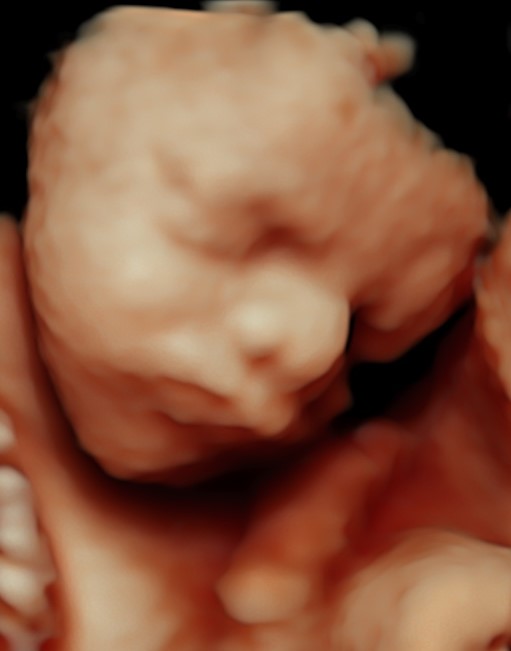

4D/5D/HD Ultrasound Gallery

Gallery